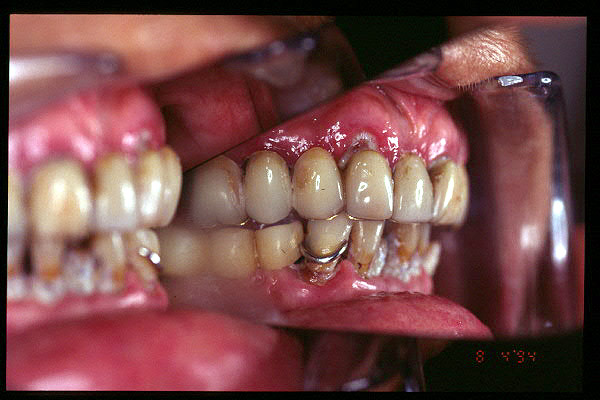

CM Prótesis fija metal-resina superior y PPR inferior. Mucha placa bacteriana